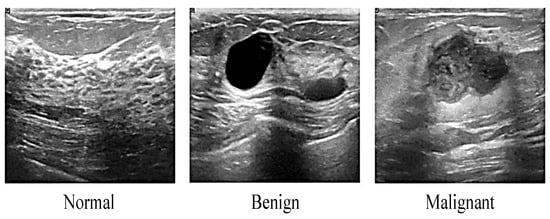

2.1.1. Ultrasound

- Al-dhabyani, W.; Gomaa, M.; Khaled, H.; Fahmy, A. Dataset of breast ultrasound images. Data Brief 2019, 28, 104863. [Google Scholar] [CrossRef] [PubMed]

| Ultrasound | Inexpensive Suitable dense breast Quick and painless Nonionizing radiation Widely available | Low resolution Low sensitivity Low specificity High operator dependency | This technology uses a high frequency of sound waves to produce an image of organs and structures within the body |

| Ultrasound | 83% (147/177) | 34% (28/81) | 67.8% (175/258) | Better than X-ray | Difficult to detect solid tumor |

| Mammogram and ultrasound | 91.5% (162/177) | 23% (19/81) | 70.2% (181/258) | Cost effective | Unwanted compression |

| Mammogram, ultrasound, and clinical | 93.2% (165/177) | 22% (18/81) | 70.9% (183/258) | Good detection | Complex signal processing |